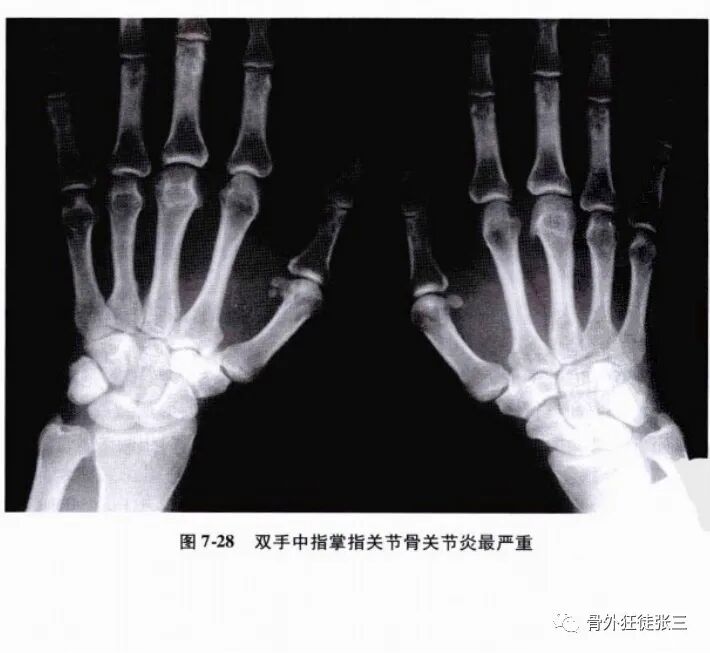

退行性绞锁多发生于中指,原因可能在于它最长,掌骨头最凸出,较其他手指承受更多的外力作用,更容易被磨损,出现骨关背炎(图7-28)。